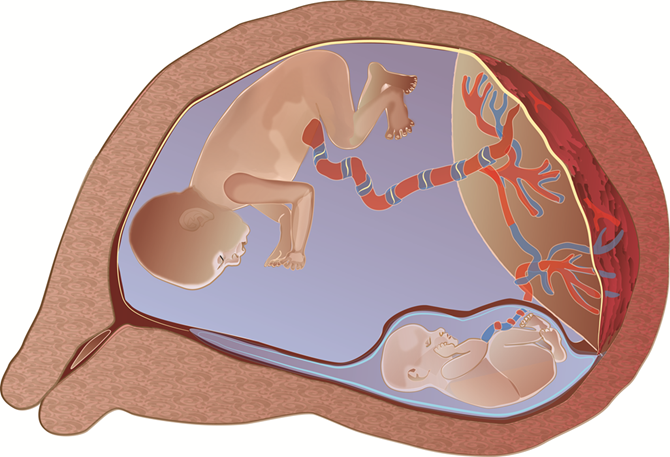

Le syndrome transfuseur transfusé (STT) est une complication unique aux grossesses gémellaires monochorioniques. Le terme « monochorionique » s’applique aux grossesses où les 2 jumeaux se partagent un seul placenta.

Dans les grossesses monochorioniques, on retrouve toujours des vaisseaux sanguins sur le placenta qui relient les deux jumeaux et par lequel il y a un échange sanguin.

Ces vaisseaux sont appelés des anastomoses placentaires. Dans la majorité des cas, l’échange de sang entre les jumeaux se fait de manière balancée.

Par contre, dans environ 10% des grossesses monochorioniques l’échange de sang n’est pas égal entre les jumeaux et cause un syndrome transfuseur-transfusé.

On observe alors que le sang circule préférentiellement d’un jumeau « donneur » vers un jumeau « receveur ». Ce syndrome peut être potentiellement très dangereux et parfois fatal pour les deux jumeaux.

Le « donneur » donne plus de sang qu’il n’en reçoit, le « receveur » en reçoit trop, ce qui va initialement causer des signes de déshydratation chez le « donneur » (diminution du liquide amniotique, vessie petite ou absente) et de surplus de liquide chez le « receveur » (augmentation du liquide amniotique, grande vessie).

Le syndrome peut éventuellement causer une insuffisance cardiaque et un décès chez un ou les 2 fœtus.

Syndrome transfuseur/transfusé

Parfois, nous observons un retard de croissance chez le jumeau donneur, ce qui est appelé un retard de croissance sélectif.